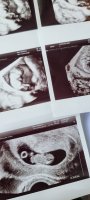

9+5 i dag. Alt så bra ut ❤️ Vi fikk se en sprellende liten bebbis med dunkende hjerte